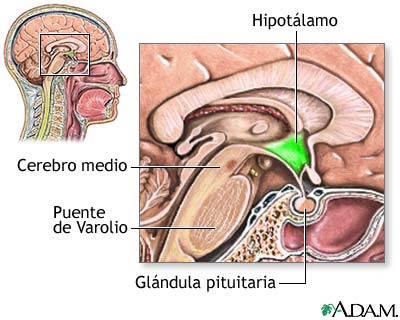

Figura 1: la glándula pituitaria ó hipófisis. Imagen recuperada de http://www.nlm.nih.gov/medlineplus/spanish/ency/esp_imagepages/17227.htm, el 17 de julio de 2007

Hoy, vamos a agregar un ingrediente más, en este peculiar programa de cocina cerebral, una estructura similar a un guisante (algunos científicos hablan del formato de pera muy pequeña ó de San Juan), con un peso de 0.5 gramos, que se denomina científicamente glándula pituitaria (también conocida como hipófisis, “crecimiento inferior”) y que se aloja en un espacio óseo, la silla turca, del hueso esfenoides, situada en la base del cráneo, en la fosa cerebral media, que conecta con el hipotálamo a través del tallo pituitario o tallo hipofisario. La etimología es sumamente curiosa para comprender anatómicamente esta microestructura de extraordinaria importancia en las mujeres y hombres, por este orden. Pituitaria significa que contiene o segrega pituita, del latín “pituita”: secreción, fluido, moco, flema, formando parte de la medicina tradicional junto a los tres “humores” restantes: sangre, bilis amarilla y bilis negra. Es una superestructura del sistema endocrino dado que ejerce un control férreo sobre ocho glándulas endocrinas que explicamos a continuación.

Esta glándula está unida al hipotálamo a través de fibras nerviosas y está formada por tres secciones: el lóbulo anterior, que representa el 80% del peso de la glándula, el lóbulo intermedio y el lóbulo posterior. El lóbulo anterior produce la hormona de crecimiento, la prolactina, que estimula la producción de leche materna después de dar a luz, la adrenocorticotrópica (ACTH), que estimula las glándulas adrenales, la estimulante de la tiroides (TSH), que estimula la glándula tiroides, la folículo-estimulante (FSH), que estimula los ovarios y los testículos al igual que la luteinizante (LH), también presente.

El lóbulo intermedio, produce la hormona estimulante de melanocitos que controla la pigmentación de la piel. El lóbulo posterior, produce la hormona antidiurética (ADH), que aumenta la absorción de agua en la sangre por medio de los riñones. Igualmente, la oxitocina, que contrae el útero durante el parto y estimula la producción de la leche materna.

Esta supercentral hormonal cumple unas funciones determinantes en el ser humano. Louann Brizendine, la autora revelación sobre el cerebro femenino, sitúa la glándula pituitaria como sexta estructura que lo caracteriza: “produce las hormonas de la fertilidad, producción de leche y comportamiento de crianza. Ayuda a poner en marcha el cerebro maternal”. Además, en el salto de la pubertad se desencadena la propulsión de las células hipotalámicas y la niña-mujer comienza a experimentar cambios que ya se repetirán día a día, mes a mes hasta la menopausia, porque “la glándula pituitaria… salta a la vida cuando los frenos químicos se sueltan en las células hipotalámicas […]. Esta liberación celular dispara el sistema hipotalámico-pituitario-ovárico” (1). El conocimiento de esta realidad recurrente en la vida de la mujer debe ayudar a los hombres a respetar íntegramente estos ciclos vitales que producen desajustes vitales, por responsabilidad directa de la naturaleza al estar muy desarrollada esta glándula en la mujer en el lóbulo anterior de la misma (recuerdo que el peso específico de esta zona desarrolla el 80% de su función diaria y perfectamente programada). No ocurre lo mismo en el cerebro masculino, porque el balanceo hormonal no pasa tanta factura en la vida ordinaria. Si se conoce bien esta estructura, se respeta. Además, se pueden poner ejemplos rotundos de este “conocimiento” cerebral femenino, basados en una hormona bastante desconocida a nivel popular pero que juega un papel trascendental en la mujer y en las relaciones de pareja. Me refiero a la oxitocina, una hormona muy atractiva para el objeto de estas publicaciones.